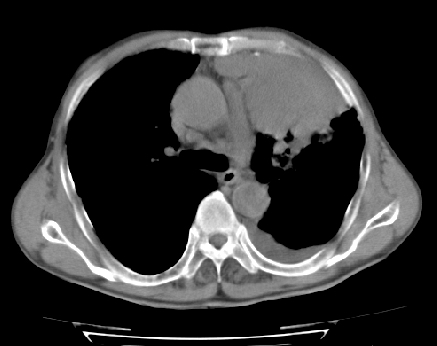

以下是引用ct诊断高手在2009-5-29 13:50:00的发言:[br]考虑左侧中央型肺癌,阻塞性肺炎伴肺不张。纵隔淋巴结转移。慢支 肺间质纤维化肺气肿。左侧胸腔积液。左侧肋骨转移?

以下是引用hhcckk在2009-5-29 14:58:00的发言:[br]左上周围型肺癌,左肺门、纵隔淋巴结转移,左侧胸腔积液,左侧肋骨转移[br]